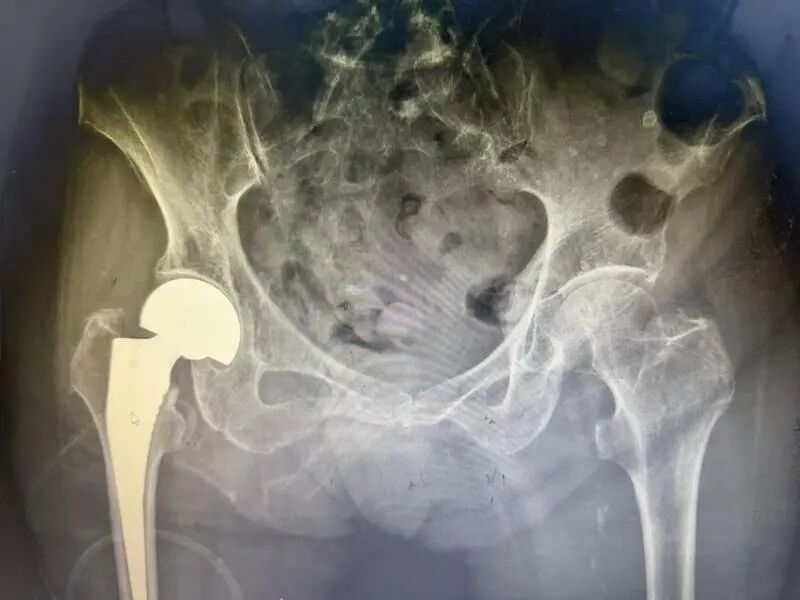

冬季是老年人骨折的高发时期。近日,90岁的张阿婆在家中不慎摔倒,导致髋关节骨折,被送往仁济医院宝山分院骨科接受手术治疗。术后恢复良好,即将出院,实现了快速康复。据悉,12月以来,该科室已连续收治9例类似高龄骨折患者。 张阿婆回忆,摔倒时自己正在正常行走,突然失去平衡跌坐在地,无法起身。经检查,她被诊断为左侧股骨颈骨折。尽管平日没有严重基础疾病,但检查显示其心脏已出现老化性改变,且当时伴有肺部感染,这些因素都可能诱发意外。 医生指出,老年人冬季活动减少,容易发生呼吸道感染,导致身体机能下降,出现头晕、乏力等症状,从而增加跌倒风险。“这种髋部骨折在老年群体中较为常见,因长期卧床可能引发严重并发症,甚至危及生命,因此常被称为‘人生最后一次骨折’。” 手术前 手术后 考虑到张阿婆年事已高,并伴有心肺功能减退和肺部感染,医院骨科团队迅速组织心内科、麻醉科、呼吸科等多学科会诊,经全面评估后,确定了“尽早手术、尽快恢复活动”的治疗方案。术后3—5天,老人就可以下床活动,逐步恢复日常生活状态。 医生提醒,冬季是老人摔倒骨折的高危季节。老年人反应能力相对下降,起夜时意识不清或视线不佳,室内地面湿滑、障碍物多,以及冬季心脑血管疾病易发等因素,均会增加摔倒风险。 为有效预防,家庭应重视适老化改造,例如减少地面高低差、保持通道畅通、在卫生间加装防滑垫和扶手;保持室内温度适宜,避免衣物过于厚重;雨雪天气尽量减少外出。同时,应关注骨质疏松的防治,在医生指导下科学补钙并进行抗骨质疏松治疗。 “建议适当开窗通风,预防呼吸道感染导致老年人心肺系统功能下降;天气晴好时增加户外活动,适度晒太阳、锻炼,增强骨骼和肌肉健康。”医生补充道,“如老人行动已显不便,可根据情况配备拐杖、助行器或轮椅。一旦出现不适,应及时就医,把握治疗黄金期。” 对于已发生髋部骨折的老年患者,医生强调,在身体状况允许的前提下,应尽早接受手术评估与治疗。目前,微创手术与快速康复理念的推广,已使更多高龄患者有机会摆脱“人生最后一次骨折”的威胁,重新获得自主活动能力。